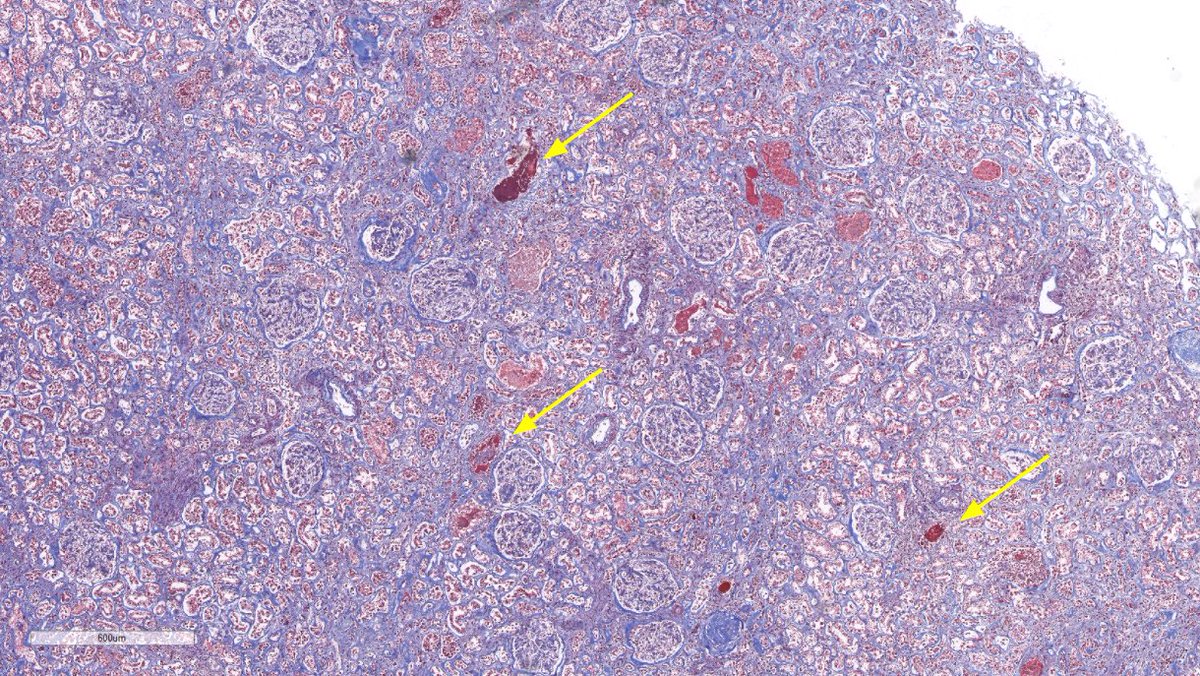

Disappearing glomeruli: loss of linear IgG in anti-GBM nephritis